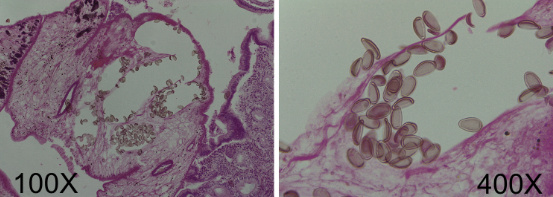

H&E stain of liver tissue

Schistosoma mansoni ova

Schistosoma mansoni ova